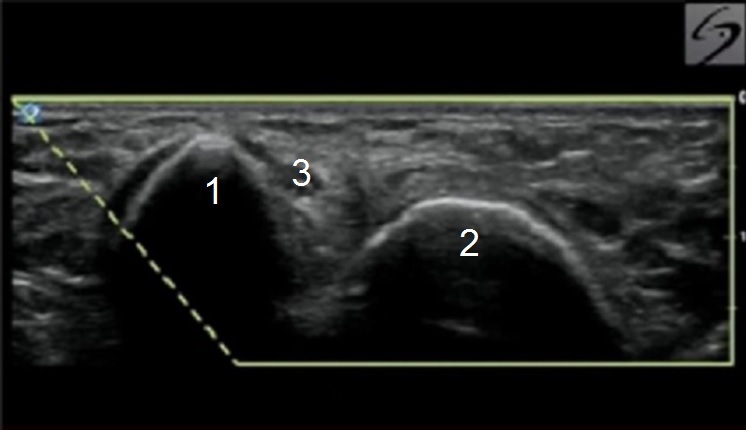

Elbow Cubital Tunnel Image

Medial Epicondyle

Olecranon Process

Ulnar Nerve